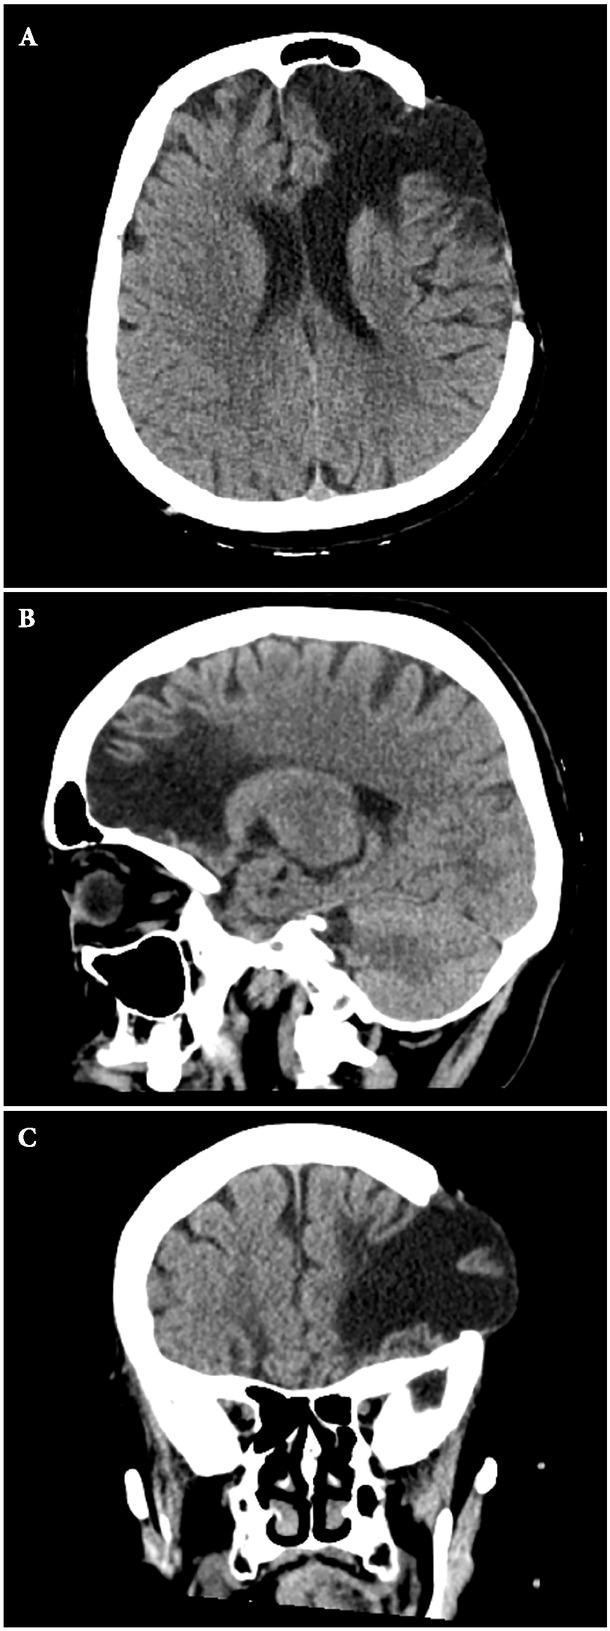

Fig. 1